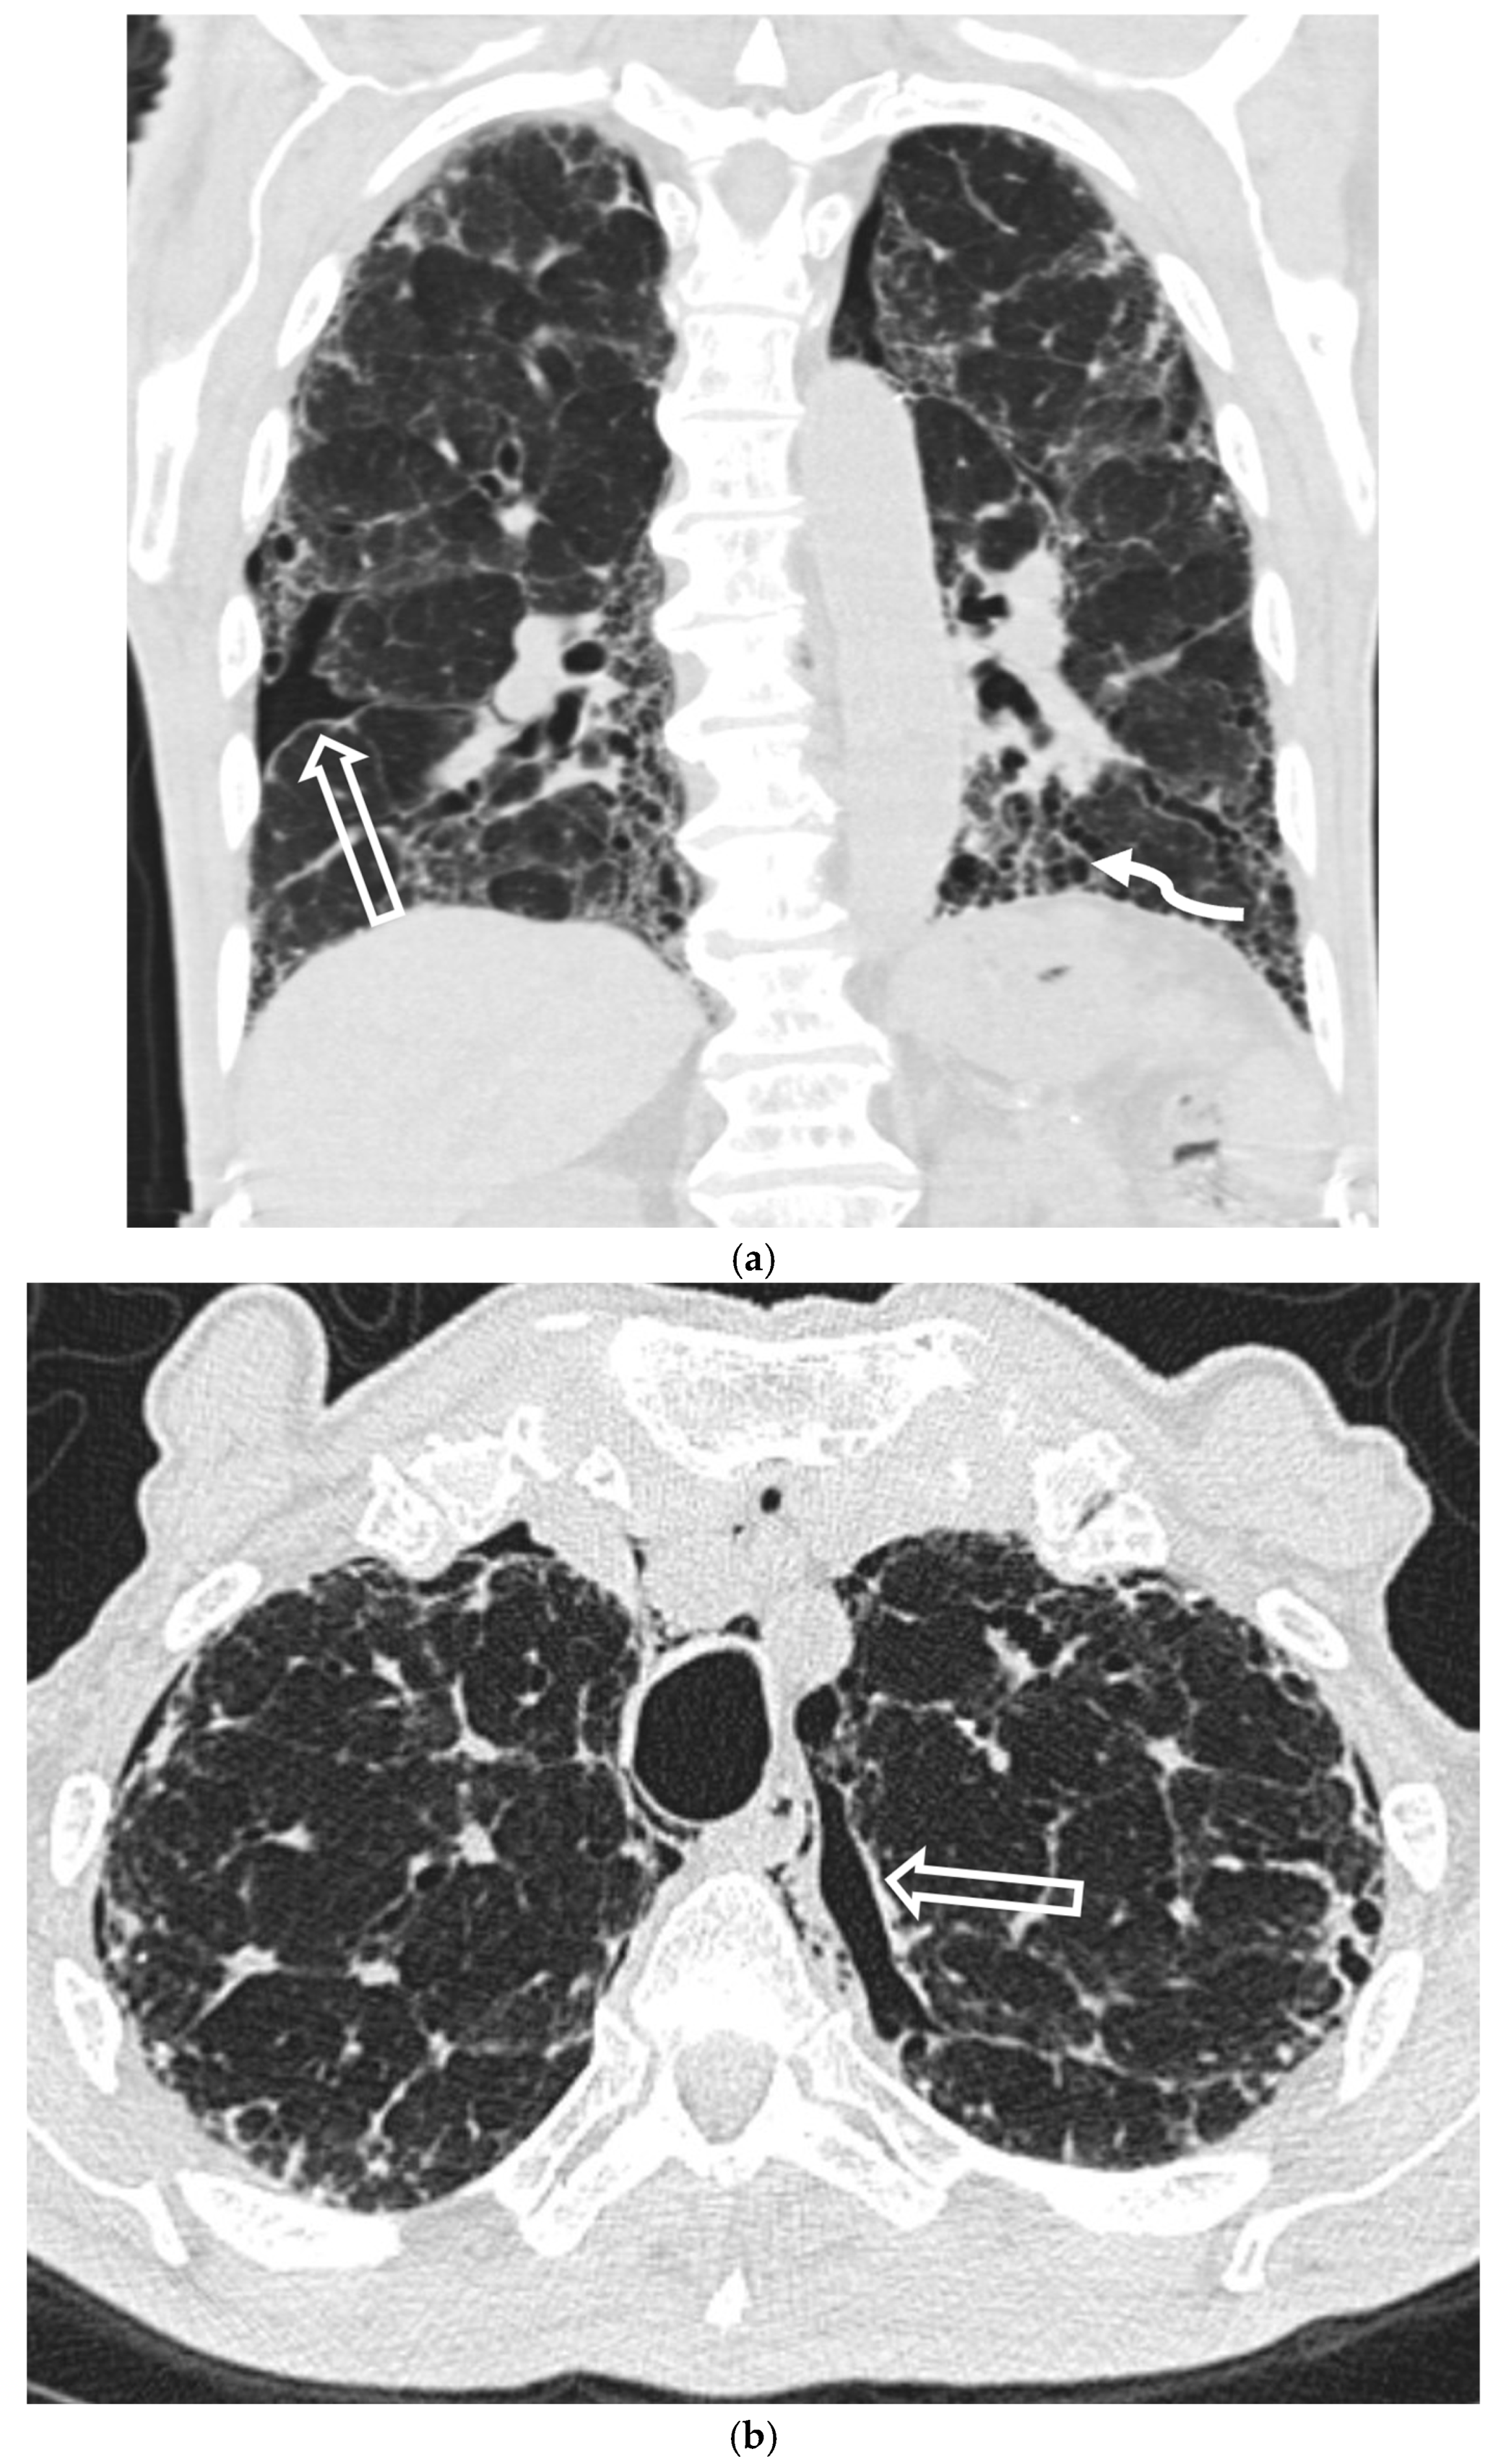

5.5. Diffuse Cystic Lung Diseases

5.5.1. Pulmonary Langerhans Cell Histiocytosis (PLCH)

5.5.2. Lymphangioleiomyomatosis (LAM)

5.5.3. Birt–Hogg–Dubé Syndrome (BHDS)